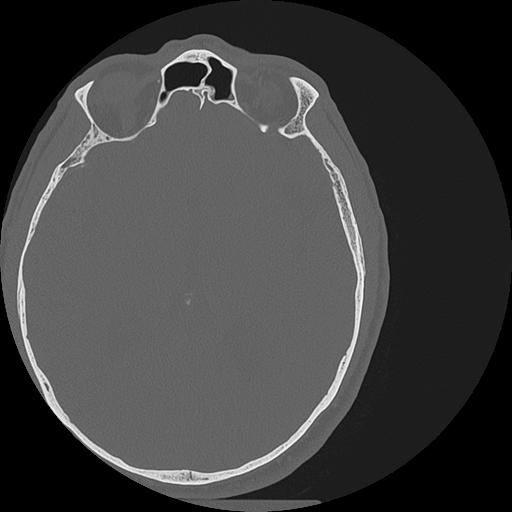

7 HUESO,,Vol,0.5,HUESO,,